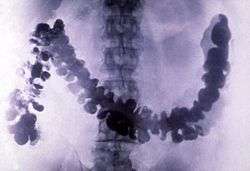

Barium has few industrial applications. Historically, it was used as a getter for vacuum tubes and in oxide form as the emissive coating on indirectly heated cathodes. It is a component of YBCO (high-temperature superconductors) and electroceramics, and is added to steel and cast iron to reduce the size of carbon grains within the microstructure. Barium compounds are added to fireworks to impart a green color. Barium sulfate is used as an insoluble additive to oil well drilling fluid. In a purer form it is used as X-ray radiocontrast agents for imaging the human gastrointestinal tract. Water-soluble barium compounds are poisonous and have been used as rodenticides.

Barium sulfate was first applied as a radiocontrast agent in X-ray imaging of the digestive system in 1908.[23]

Barium sulfate has a low toxicity and relatively high density of ca. 4.5 g/cm3 (and thus opacity to X-rays). For this reason it is used as a radiocontrast agent in X-ray imaging of the digestive system ("barium meals" and "barium enemas").[11]: 4–5 Lithopone, a pigment that contains barium sulfate and zinc sulfide, is a permanent white with good covering power that does not darken when exposed to sulfides.[29]